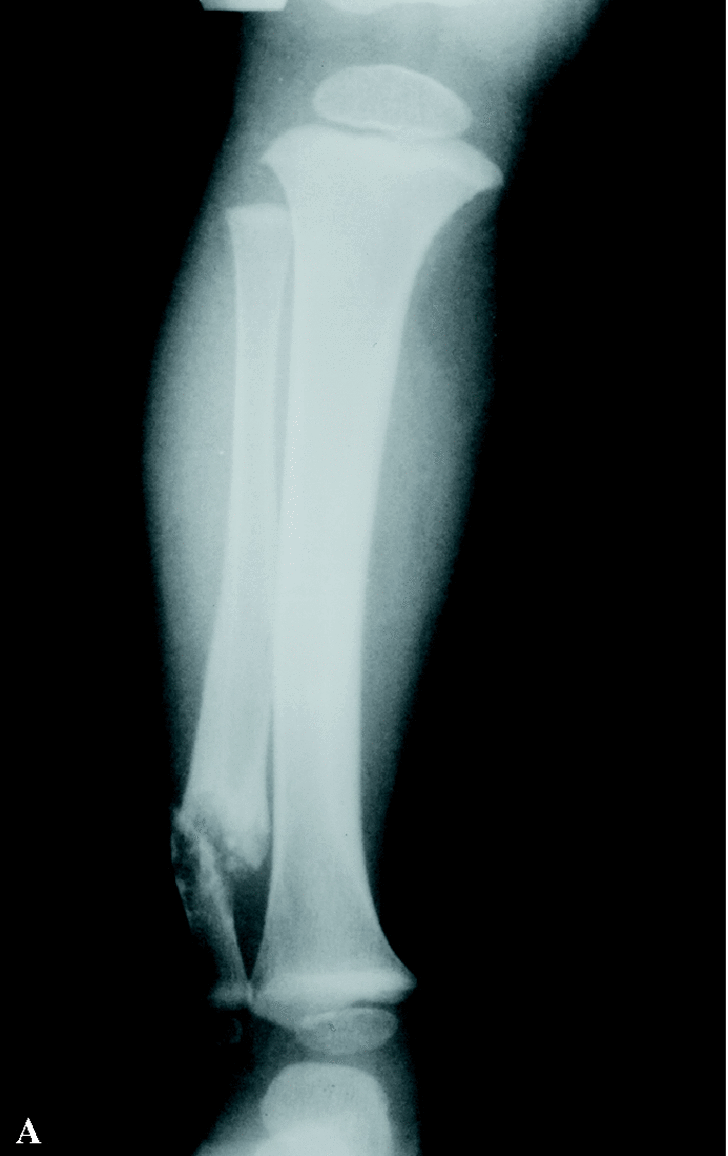

Paciente varón de 13 años que acude por primera vez a nuestras consultas con el diagnóstico previo de pseudoartrosis congénita de peroné con deformidad en valgo de tobillo derecho, sin una neurofibromatosis asociada. A los 16 meses de edad acudió al traumatólogo por tumoración en cara externa de tobillo derecho clínicamente asintomática. Tras realizar un estudio radiológico se diagnosticó de pseudoartrosis congénita de peroné (Fig. 1). Fue intervenido quirúrgicamente resecándose el foco de pseudoartrosis, sin aporte de injerto. A los 11 años, fue nuevamente valorado por presentar importante valgo de tobillo derecho; en la radiografía simple se apreció persistencia de pseudoartrosis peronea. Durante la cirugía se realizó una limpieza del tejido fibroso de la pseudoartrosis, añadiendo en esta ocasión injerto óseo de cresta iliaca, realizándose también una epifisiodesis medial de la tibia con tornillo AO (Fig. 2). Se inmovilizó con yeso. No mejora tras la cirugía.

Figura 1. Proyecciones antero-posterior (A) y lateral (B) de la tibia y el peroné derechos a los 16 meses de edad, en las que se aprecian la situación de la pseudoartrosis previa a cirugía.